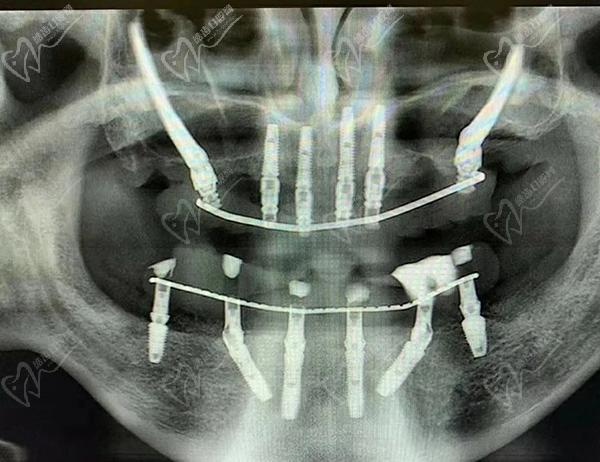

接下來,醫(yī)生會在必要的位置上植入種植體。這些種植體充當(dāng)人工牙根,用于支撐和固定新的牙齒。采用數(shù)字化智能種植技術(shù),上下牙頜各僅需要4-6顆植體就能恢復(fù)半口牙14顆牙齒。